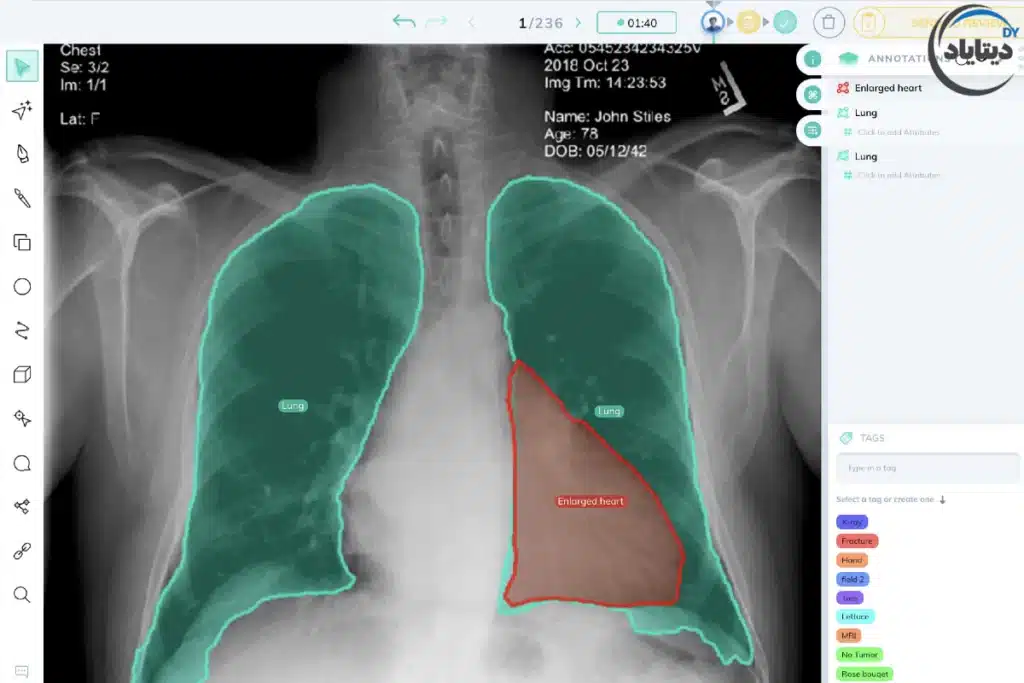

۳. تصویربرداری پزشکی (Medical Imaging)

در حوزه سلامت، بینایی کامپیوتر به عنوان یک ابزار قدرتمند غربالگری و تشخیصی عمل میکند. سیستمهای هوش مصنوعی با تحلیل تصاویر پزشکی (مانند MRI، سیتیاسکن و تصاویر پاتولوژی) از بخشبندی تصویر برای تعیین مرزهای دقیق تومورها، ضایعات و بافتهای بیمار استفاده میکنند. این سیستمها میتوانند از طریق دستهبندی تصویر (Image Classification) در تشخیص زودهنگام بیماریهای پیچیده (مانند رتینوپاتی دیابتی یا انواع سرطان) به پزشکان کمک کرده و سرعت و دقت تشخیص را به شکل چشمگیری افزایش دهند..